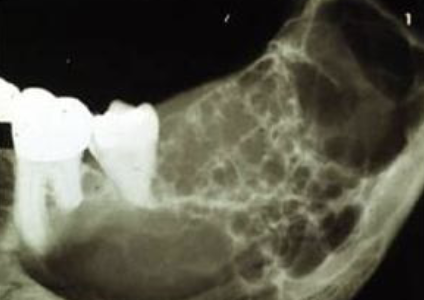

how would you describe this radiographic lesion?

a multilocular radiolucent lesion